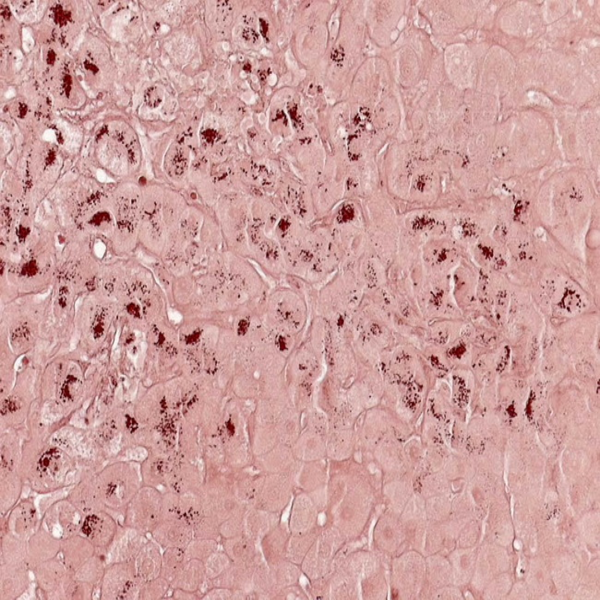

- General and specialized tissue and cell staining

- Perform tunnel technique to evaluate apoptosis

Histological methods includes sample processing in the pathology laboratory, preparation of the slide and its examination under a microscope, sample fixation, molding, microtome cutting, staining and assembly of the slides.